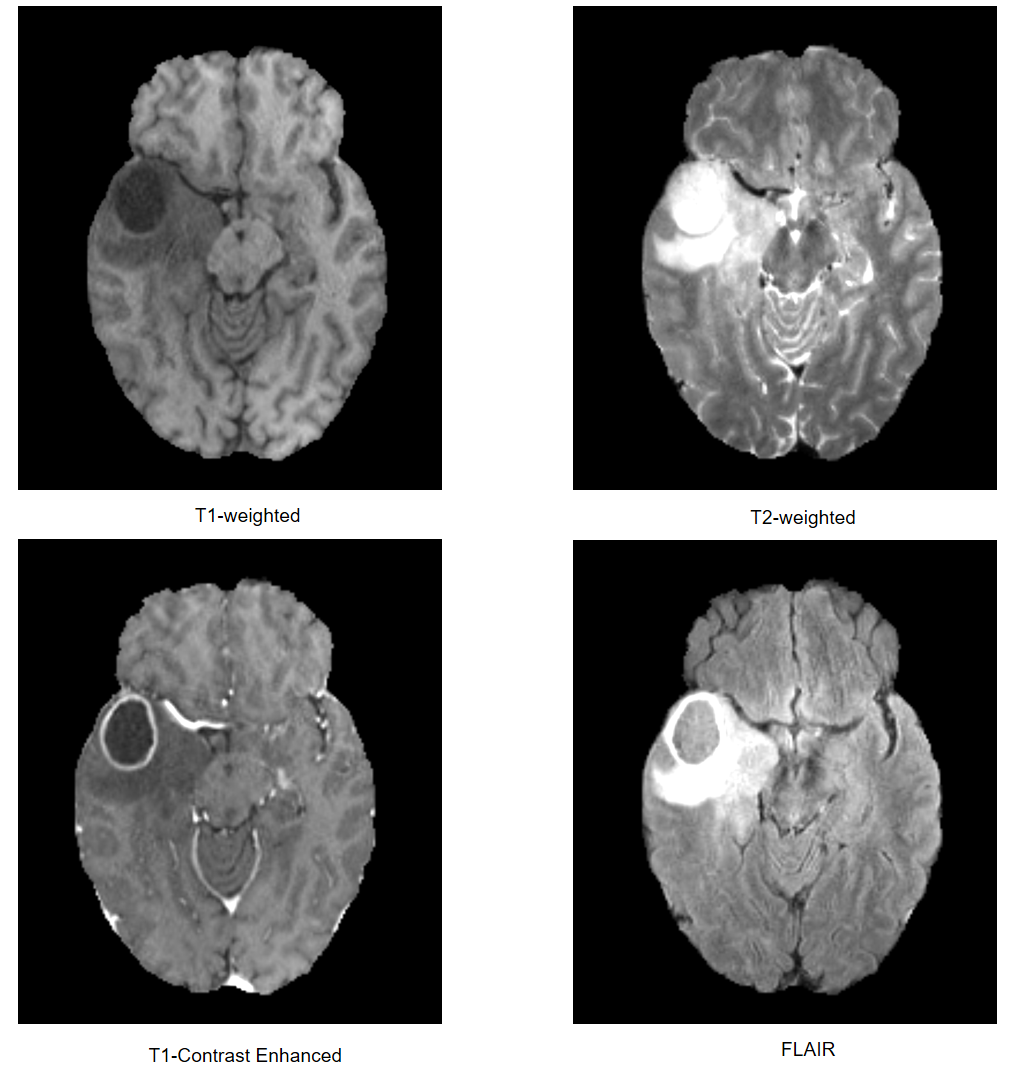

The brain tumor segmentation challenge (BraTS) [1, 2, 3, 4, 5] aims to accelerate the research and development of reliable methods for automatic brain tumor segmentation by providing a large 3D mpMRI dataset with ground truth annotated by multiple physicians. This year, BraTS 2020 provides 369369369 cases for model training and 125 cases for model validation. The MRI scans were collected from 19 institutions and acquired with different protocols, magnetic field strengths and manufacturers. For each patient, a native T1-weighted, a post-contrast T1-weighted, a T2-weighted and a T2 Fluid-Attenuated Inversion Recovery (FLAIR) were provided. These images were rigidly registered, skull-stripped and resampled to 1×1×11111\times 1\times 1 mm isotropic resolution with image size of 240×240×155240240155240\times 240\times 155. Three tumor subregions, including the enhancing tumor, the peritumoral edema and the necrotic and other non-enhancing tumor core, were manually annotated by one to four raters following the same annotation protocol and finally approved by experienced neuro-radiologists.

Refer to caption

Figure 1: An example of MRI modalities used in BraTS 2020 challenge